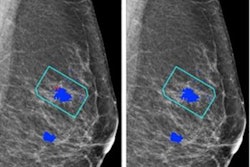

Ramtohul and co-authors wanted to find out whether multiparametric MRI-based radiomic features could help differentiate HER2-zero, HER2-low, and HER2-positive tumors. They tested their method on women with breast cancer who underwent MRI at two different centers between 2020 and 2022. The team also performed tumor segmentation and radiomic feature extraction on T2-weighted and dynamic contrast-enhanced T1-weighted images.

The team extracted a total of 101 features from 2D T2-weighted images and 107 features from 3D T1-weighted images. After unsupervised correlation analysis, 31 features were entered into the feature selection model. This included 14 T2-weighted and 17 dynamic contrast-enhanced T1-weighted images. The team obtained a radiomic signature using logistic regression of the top seven least absolute shrinkage and selection operator (LASSO)-selected features. This separated HER2-low and HER2-positive cancers from HER2-zero cancers.